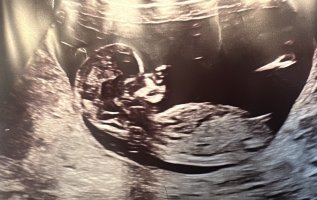

Nei, man kan dessverre ikke se det her. Man må se baby i sideprofil uten at lårbenet er synligNoen som klarer å se hvilket kjønn dette er?Vis vedlegget 466071

Vil dere gjette ut fra teorien hva kjønnet kan være? blir litt gal og sykehuset ville ikke si det fordi det var for tidlig..

Det er det jeg selv har følt hele veien også, men vært veldig usikker på hva jeg skal se på og måle ut fra bildetJente![]()

@lyse gul hva tror du ?Det er det jeg selv har følt hele veien også, men vært veldig usikker på hva jeg skal se på og måle ut fra bildet![]()

Her gjemmer det seg en gutt gitt! Ikke til å ta feil av nå, haha. Så tydeligvis var det for tidlig ultralyd sistHar disse ogsåJeg kan ikke se noen nub på disse bildene, så det er ingen ting å gjette på desverre. Har du flere bilder?

nå har jeg fått bekreftet om at det er liten jenteHar disse ogsåhåper man kan se det på et av bildene hvertfall (alle de er tatt samme dag 12+3) @lyse gul